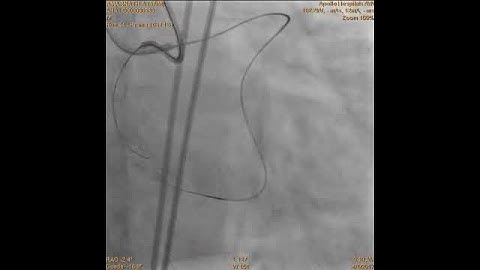

Case 260: Manual of CTO PCI - Retrograde through LIMA